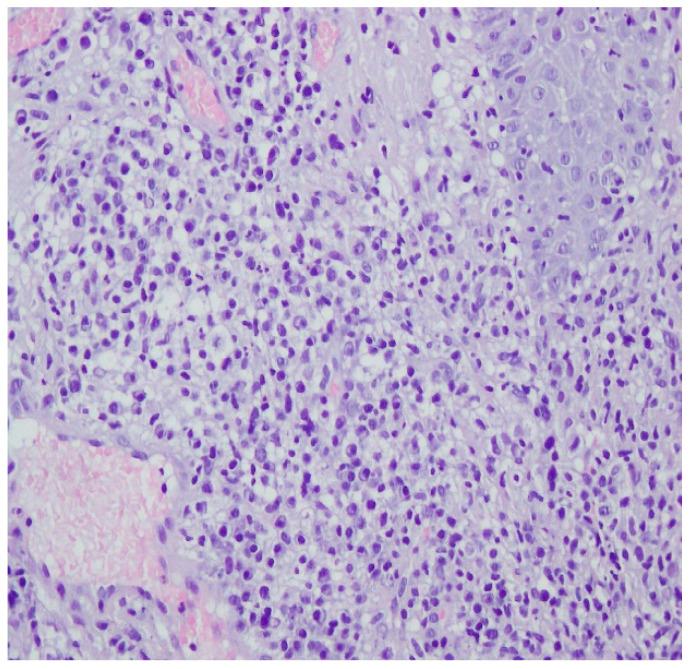

三期梅毒诊断难点:病例报告并文献复习

Challenges in the Diagnosis of Tertiary Syphilis: Case Report with Literature Review.

Tertiary syphilis is a large diagnostic challenge. It is rarely the case that it affects the skin, bone tissue and the eyes at the same time. The presented case shows that extensive symptomatology of syphilis poses a challenge in making a proper diagnosis in patients whose history does not suspect STDs. The study aims to present the case of a young woman hospitalized with a suspected autoimmune disease, diagnosed with symptomatic late syphilis with involvement of the skin, bones and eyes.

摘要

三期梅毒是一个重大的诊断挑战。它很少同时影响皮肤、骨骼组织和眼睛。所呈现的病例表明,在那些病史不怀疑性传播疾病的患者中,广泛的梅毒症状表现给正确诊断带来了挑战。本研究旨在介绍一例年轻女性住院的病例,该女性被怀疑患有自身免疫性疾病,后被诊断为症状性晚期梅毒,涉及皮肤、骨骼和眼睛。